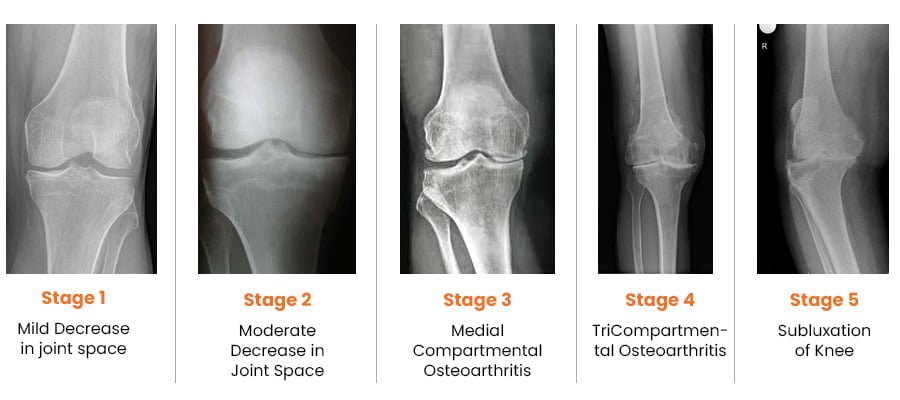

Osteoarthritis (OA) of knee occurs due to wear and tear of cartilage. It is usually due to aging and seen mostly in elderly people. Females usually get affected at slightly earlier age than males. OA can also occur in some cases due to injury in the knee, congenital malformation or due to any other diseases affecting other joints of the body.

It is due to progressive wear and tear leading to loss of cartilage in knee joint. Most commonly, this is due to the aging. In some cases, damage to the cartilage may occur due to rheumatoid and other inflammatory arthritis, trauma, infection, gout, or any other condition affecting knee joint. Those who are over-weight have more chances of developing arthritis in their knees.

Your doctor will do clinical examination of knee joint, hip joint, spine and other joints of your body. X-rays of both knees will be performed. Occasionally, MRI of the Knee joint and few blood investigations may be required as per their underlying problem.